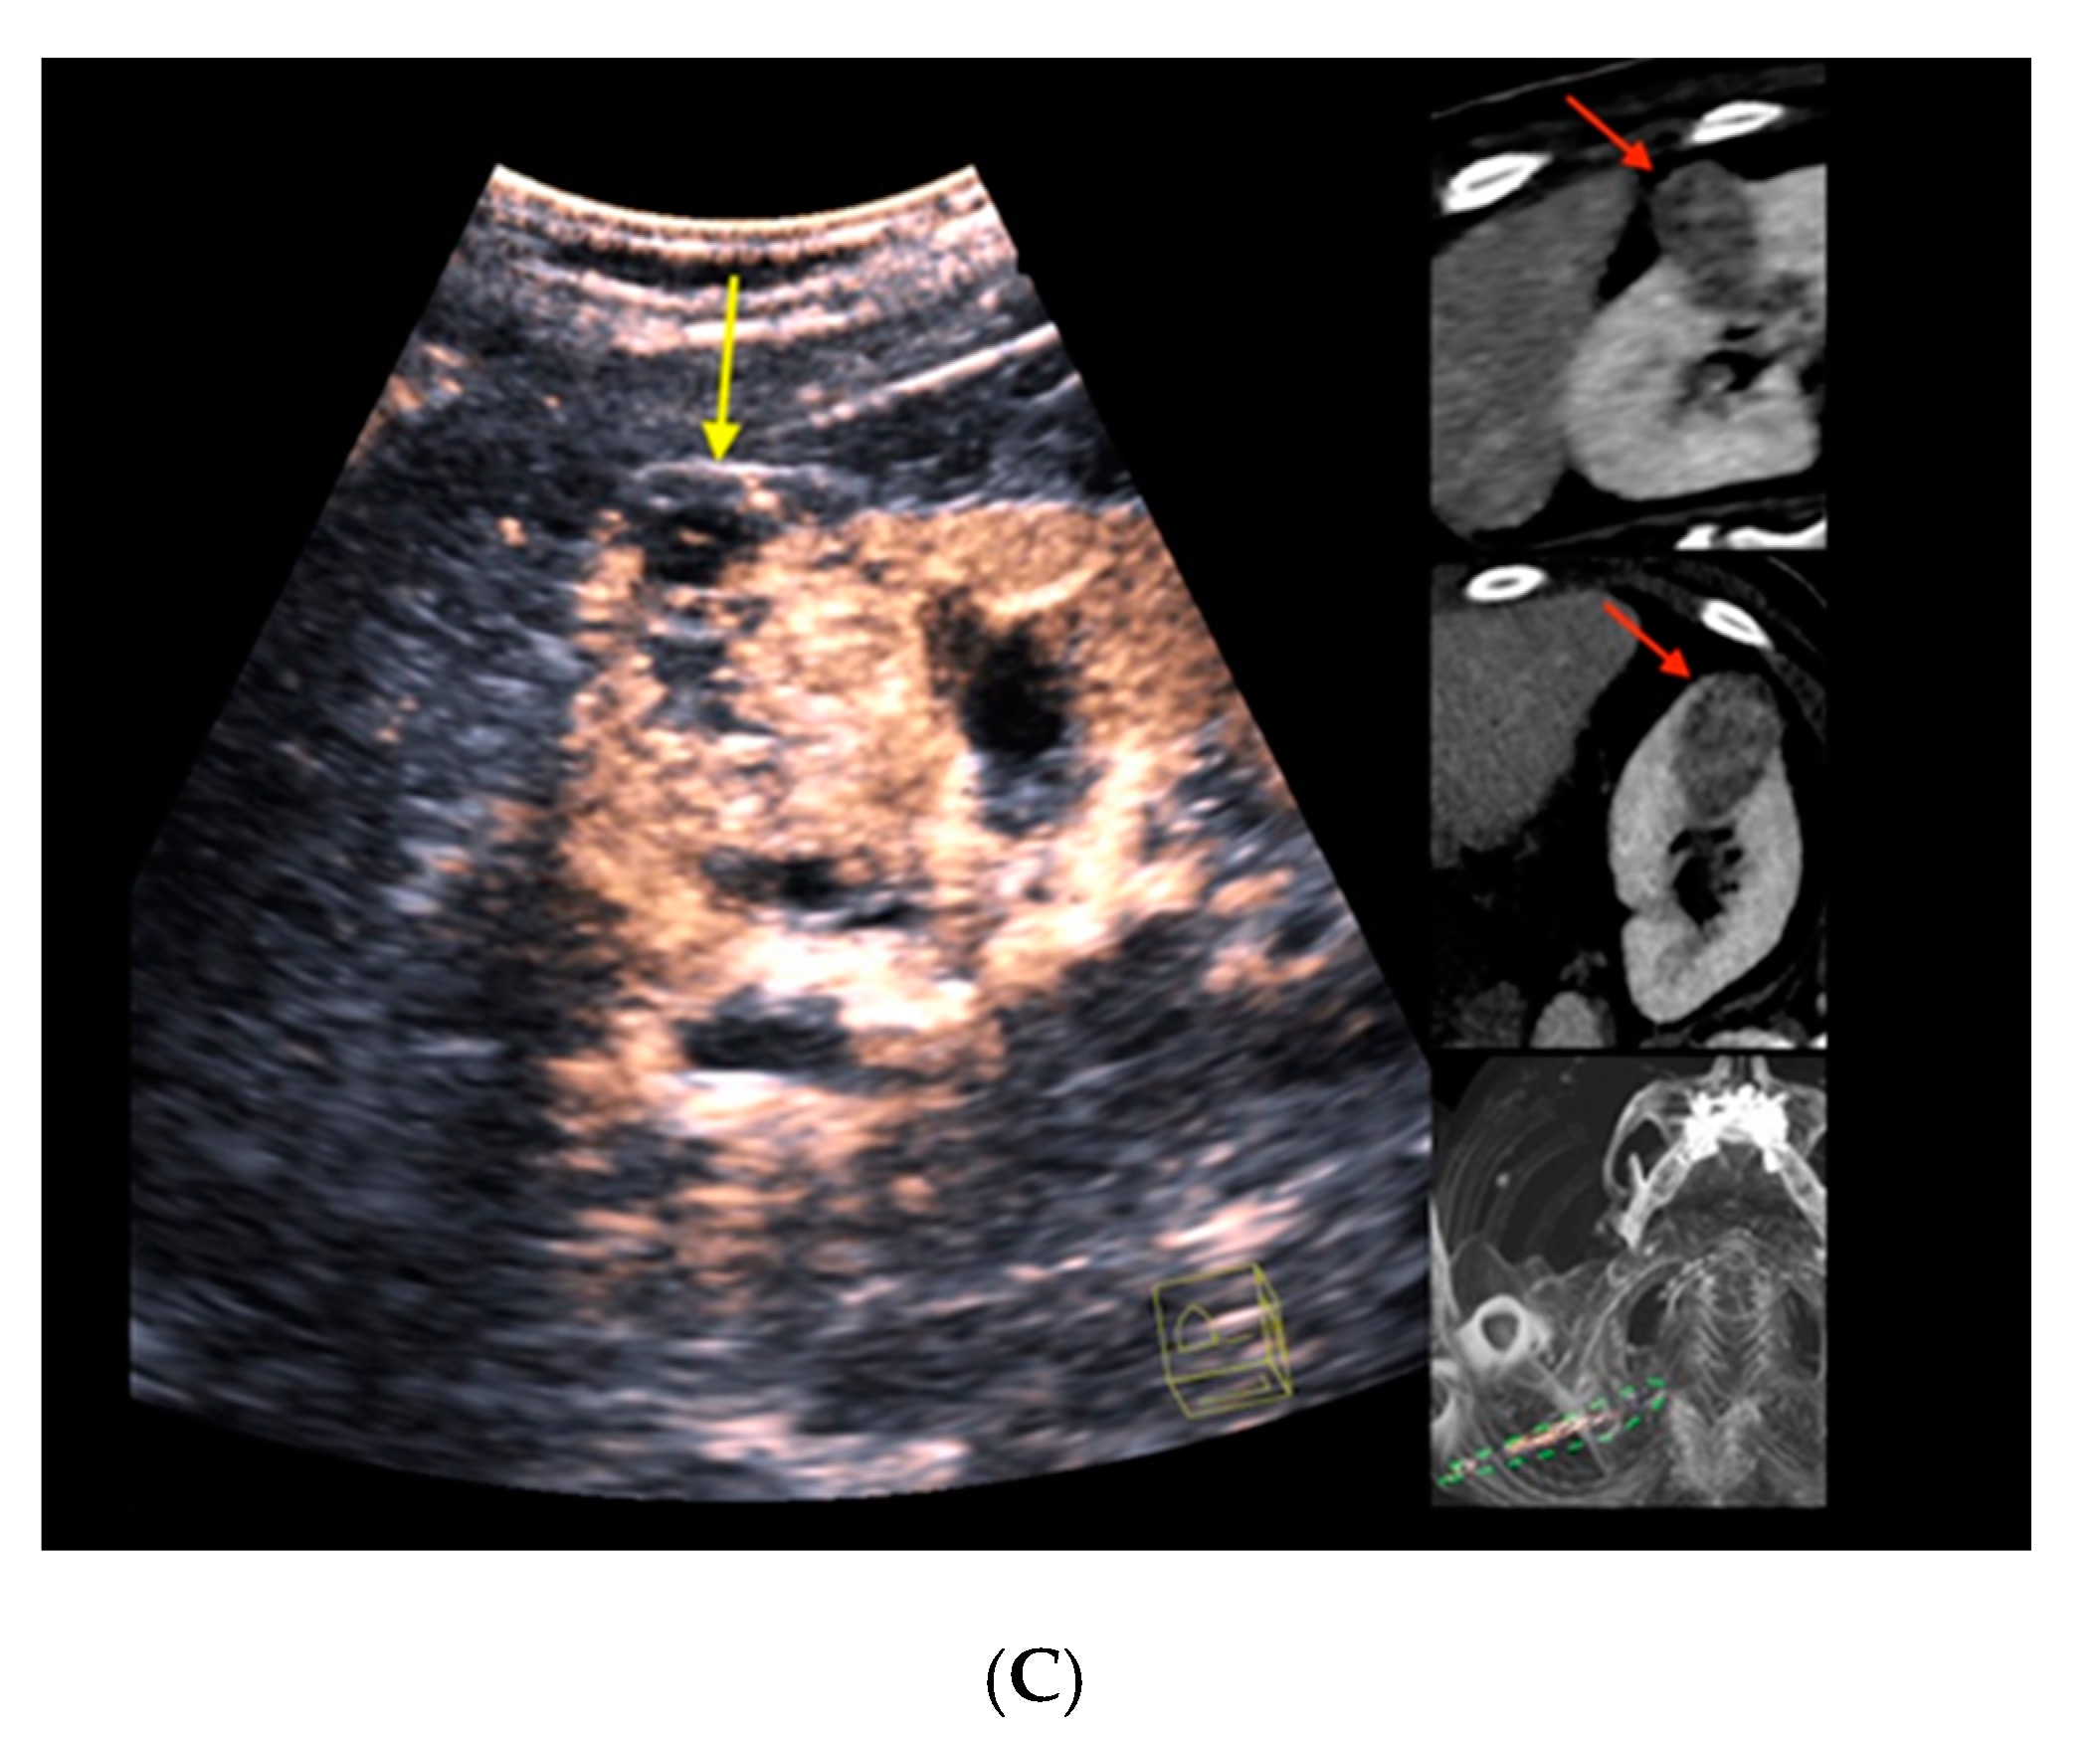

Figure 2 depicts the morphological correlates from CT/CEUS-fusion imaging of a clear-cell RCC. An overview of the findings from cross-sectional imaging (CT/MRI) and corresponding correlates by fusion imaging of the included renal liver lesions is depicted in Table 2.

Figure 2.

Real-time CT-/CEUS-fusion imaging of a complex renal cystic lesion. (A) Known complex renal cystic lesion with indicated septations and solid components in the right kidney from previous contrast-enhanced CT (left, red arrow) is displayed in a side-by-side mode with native B-mode (right, yellow arrow) by a high-end ultrasound system. (B) Additional Color Doppler did not reveal hypervascularization of the lesion (yellow arrow). The software interface of the ultrasound device showed four different images: the real-time Color Doppler image (left, maximized), the CT imaging dataset in sagittal (upper right) and axial (middle right) reformation (lesion marked by red arrows), and a real-time 3D navigation of the Fusion Imaging (lower right). (C) Contrast-enhanced ultrasound allowed for visualization of early arterial microperfusion of solid components of the lesion, implicating malignancy (left, maximized), (lesion marked by red arrows in corresponding CT images). The patient underwent partial nephrectomy. Histopathology, finally, revealed underlying clear-cell renal cell carcinoma.